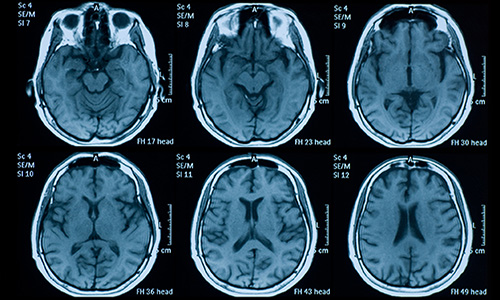

NIH (NINDS)   —   R21NS129147

Alberts, Jay

“The impact of exercise on subthalamic nucleus neural activity in Parkinson's disease”